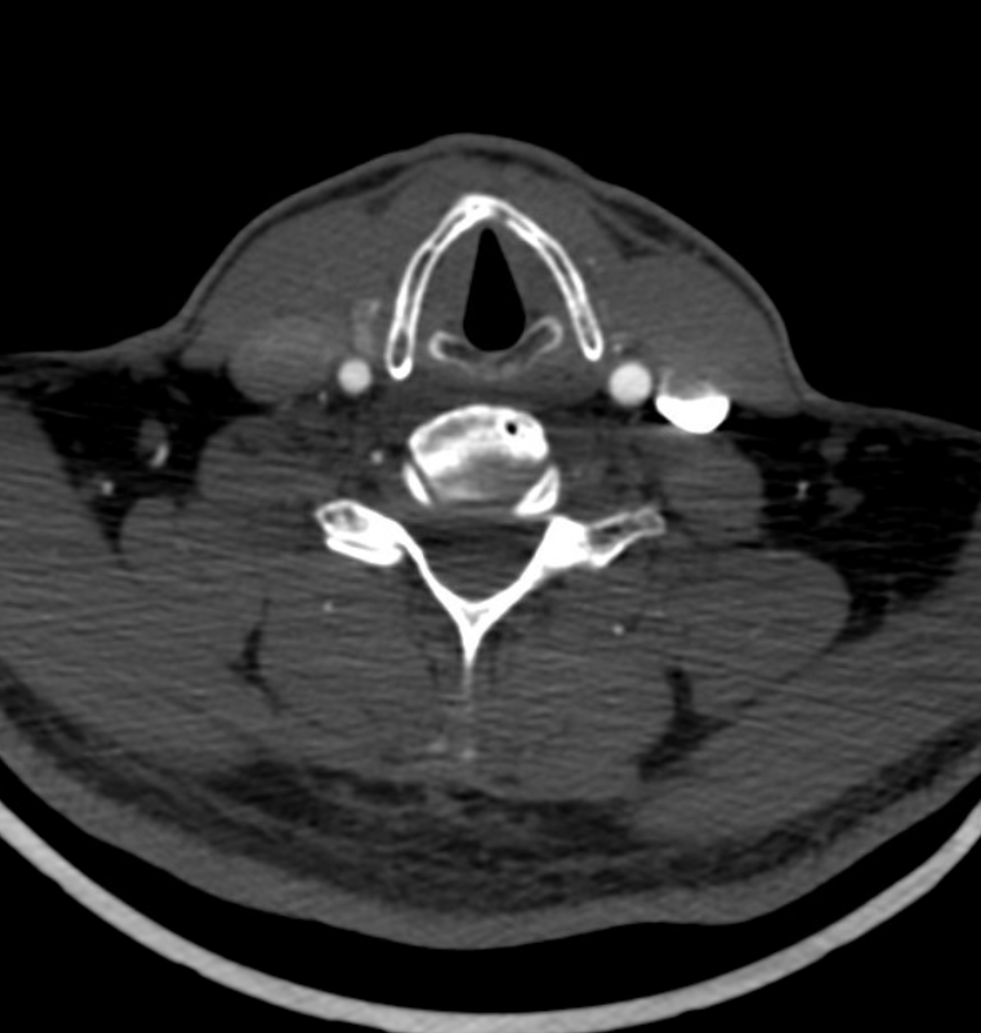

The sigmoid sinuses are not always of the same caliber as the transverse ones, especially when a large vein of Labbe empties into the proximal sigmoid sinus to enlarge it substantially as compared with its transverse tributary. Extensive emissary veins (mastoid, occipital, condylar) often drain in part and occasionally in toto the transverse-sigmoid sinus complex, and the corresponding jugulars may be hypoplastic. Isolated findings of this nature are rarely due to consequences of pathologic shunting, and looking on bone windows for emissary channels can confirm this as a non-pathologic anatomical disposition.

Emissary Veins

Emissary Veins These can sometimes be very prominent, especially when there is associated absence or compression of the jugular vein (this structure can be frequently compressed between the C1 lateral mass and the styloid process). They can become quite efficient. More interesting, perhaps, are the less frequently appreciated but sometimes quite important emissary veins located elsewhere, for example over the frontoparietal convexities. Dry skull specimens sometimes sport a few seemingly random holes on the top, which are emissary foramina for these veins, typically connected to the superior sagittal sinus. The single emissary vein below (white) traverses the skull, marked by its fainter appearane due to skull density. Once part of the scalp, it splits into the ipsilateral (light blue) and contralateral (purple) channels which ultimately empty into the ipsilateral (dark blue) and contralateral (pink) pterygopalatine fossae venous plexuses. The emissary vein can be appreciated without the stereo capability by its course anterior to the sagittal sinus. Since the sagittal sinus is a midline structure, anything anterior to it on a standard lateral projection has to be either intra-osseous or trans-osseous.

These can sometimes be very prominent, especially when there is associated absence or compression of the jugular vein (this structure can be frequently compressed between the C1 lateral mass and the styloid process). They can become quite efficient. More interesting, perhaps, are the less frequently appreciated but sometimes quite important emissary veins located elsewhere, for example over the frontoparietal convexities. Dry skull specimens sometimes sport a few seemingly random holes on the top, which are emissary foramina for these veins, typically connected to the superior sagittal sinus. The single emissary vein below (white) traverses the skull, marked by its fainter appearane due to skull density. Once part of the scalp, it splits into the ipsilateral (light blue) and contralateral (purple) channels which ultimately empty into the ipsilateral (dark blue) and contralateral (pink) pterygopalatine fossae venous plexuses. The emissary vein can be appreciated without the stereo capability by its course anterior to the sagittal sinus. Since the sagittal sinus is a midline structure, anything anterior to it on a standard lateral projection has to be either intra-osseous or trans-osseous.